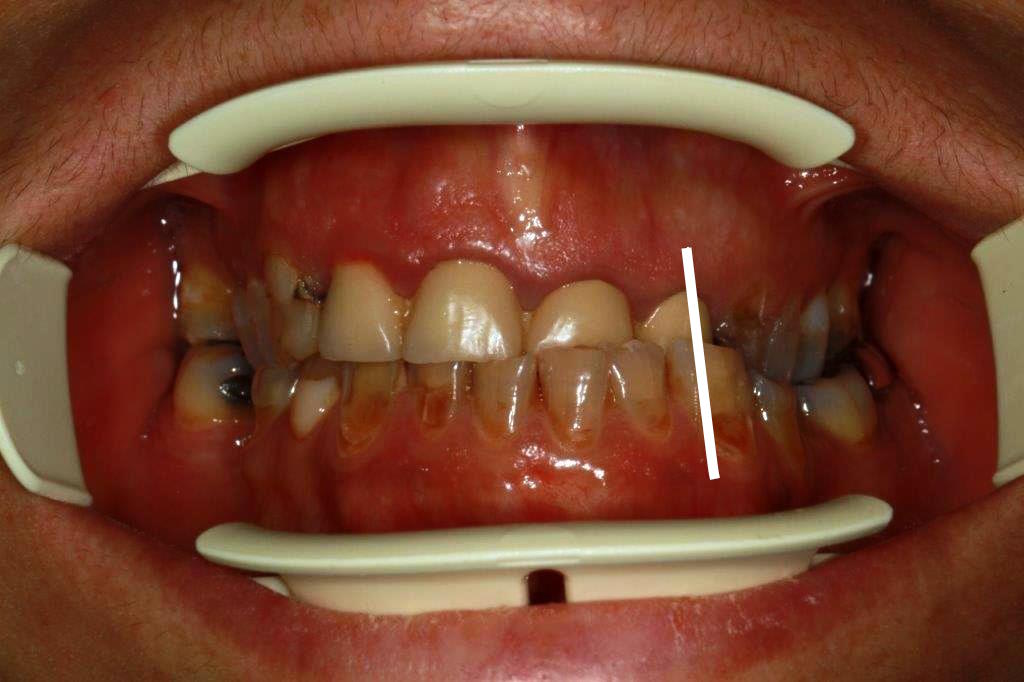

charge ton fusil enlaye.... taille + empreinte et provisoire résine (photos avant la finition des provisoires)

avec les prov on verra apparaître les pistes de friction , il n'y a pas de pb , ils sont au contact , au fait ? ce qui ne serait pas gênant si ç est des provs

la 23 est un peu violente , non ,?

Très légère souocclusion et on laisse tranquille .

23 un peu hot oui

tu es en protection de groupe ?

du fait de la prognathie, la désocclusion ne ce fait pas de façon standard, je vais travailler là-dessus pour avoir un truc fiable dans le temps.

pour 23 c'est au départ pour le look effectivement en sachant que c'est simple à réduire, vs compliqué à rallonger